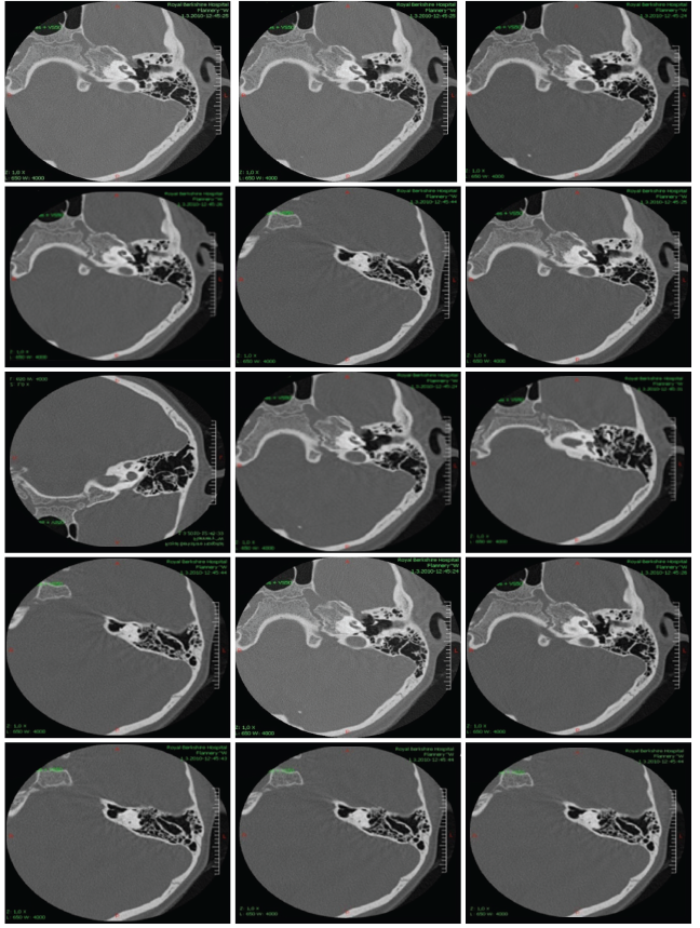

We are presenting three of our patients with this rare syndrome. First, we present a girl, aged four years at diagnosis, who has fulfilled BOR diagnostic criteria manifesting three cardinal features: unilateral renal hypoplasia, bilateral cervical branchial cysts and a hearing loss. Family history was negative for hearing loss, neck fistula and kidney problems. She has a younger healthy brother. She has achieved regular milestones, except development of speech, which was delayed and non-intelligible for the unknown listeners. Her intelligence and growth were normal at the age of four years. In-utero presence of unilateral renal hypoplasia was noticed. Lateral fistula on the left neck-side was operated on at the age of three years. Preauricular pits were present on both sides. Otoscopic and rhinoscopic findings were regular bilaterally. Throat was showing velopharyngeal insufficiency without having signs of submucous cleft palate as a minor criteria. Tympanogram was type A on both sides and acoustic reflex was absent bilaterally at all probe intensities. Transient otoacoustic emissions were not registered. Tonal audiometry showed a conductive hearing loss bilaterally with pure tone average about 75 dB for air conduction. Brainstem evoked auditory potentials confirmed this finding. Caloric test showed regular function of the both labyrinths. Computerised tomography of temporal bones confirmed malformations in both middle ears (Figure 1). Genetic investigations in the UK have confirmed the presence of BOR syndrome registering the EYA 1 mutation at 8q chromosome (Figure 2).

Figure 2: Computerised tomography of temporal bones belonging to a four year old girl with Branchio Oto Renal

syndrome who has conductive hearing loss as a conseqence of ossicle malformations.